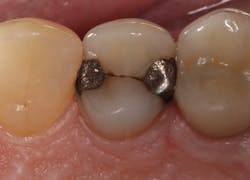

I have found that most posterior teeth can be restored using a single shade. In cases where the tooth structure is very discolored, coupled with a shallow tooth preparation, I opt for an opaque layer beneath my core shade. For anterior cases, the enamel shades offer enough translucency to give the restoration a lifelike appearance. I tend to opt for a core shade to restore chipped incisal edges, and the results have been terrific. Nothing’s worse than a patient coming back with an anterior composite restoration that didn’t hold up; it leads to patients losing confidence in your skills, sometimes negative reviews, wasted chair time, and lost profitability. Polishing this composite is very efficient and effective, and so far, it’s maintained its shine. From my assistants’ perspectives, simplifying my systems made it easier to learn, maintain inventory, and prepare for direct restorations. From my perspective, simplifying composite restorations allows me to reduce chair time, minimize waste, and predictably and efficiently place restorations that my patients love.

Results